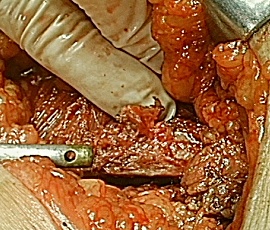

[肋骨骨折] 手術:肋骨骨折観血的手術

手術画像